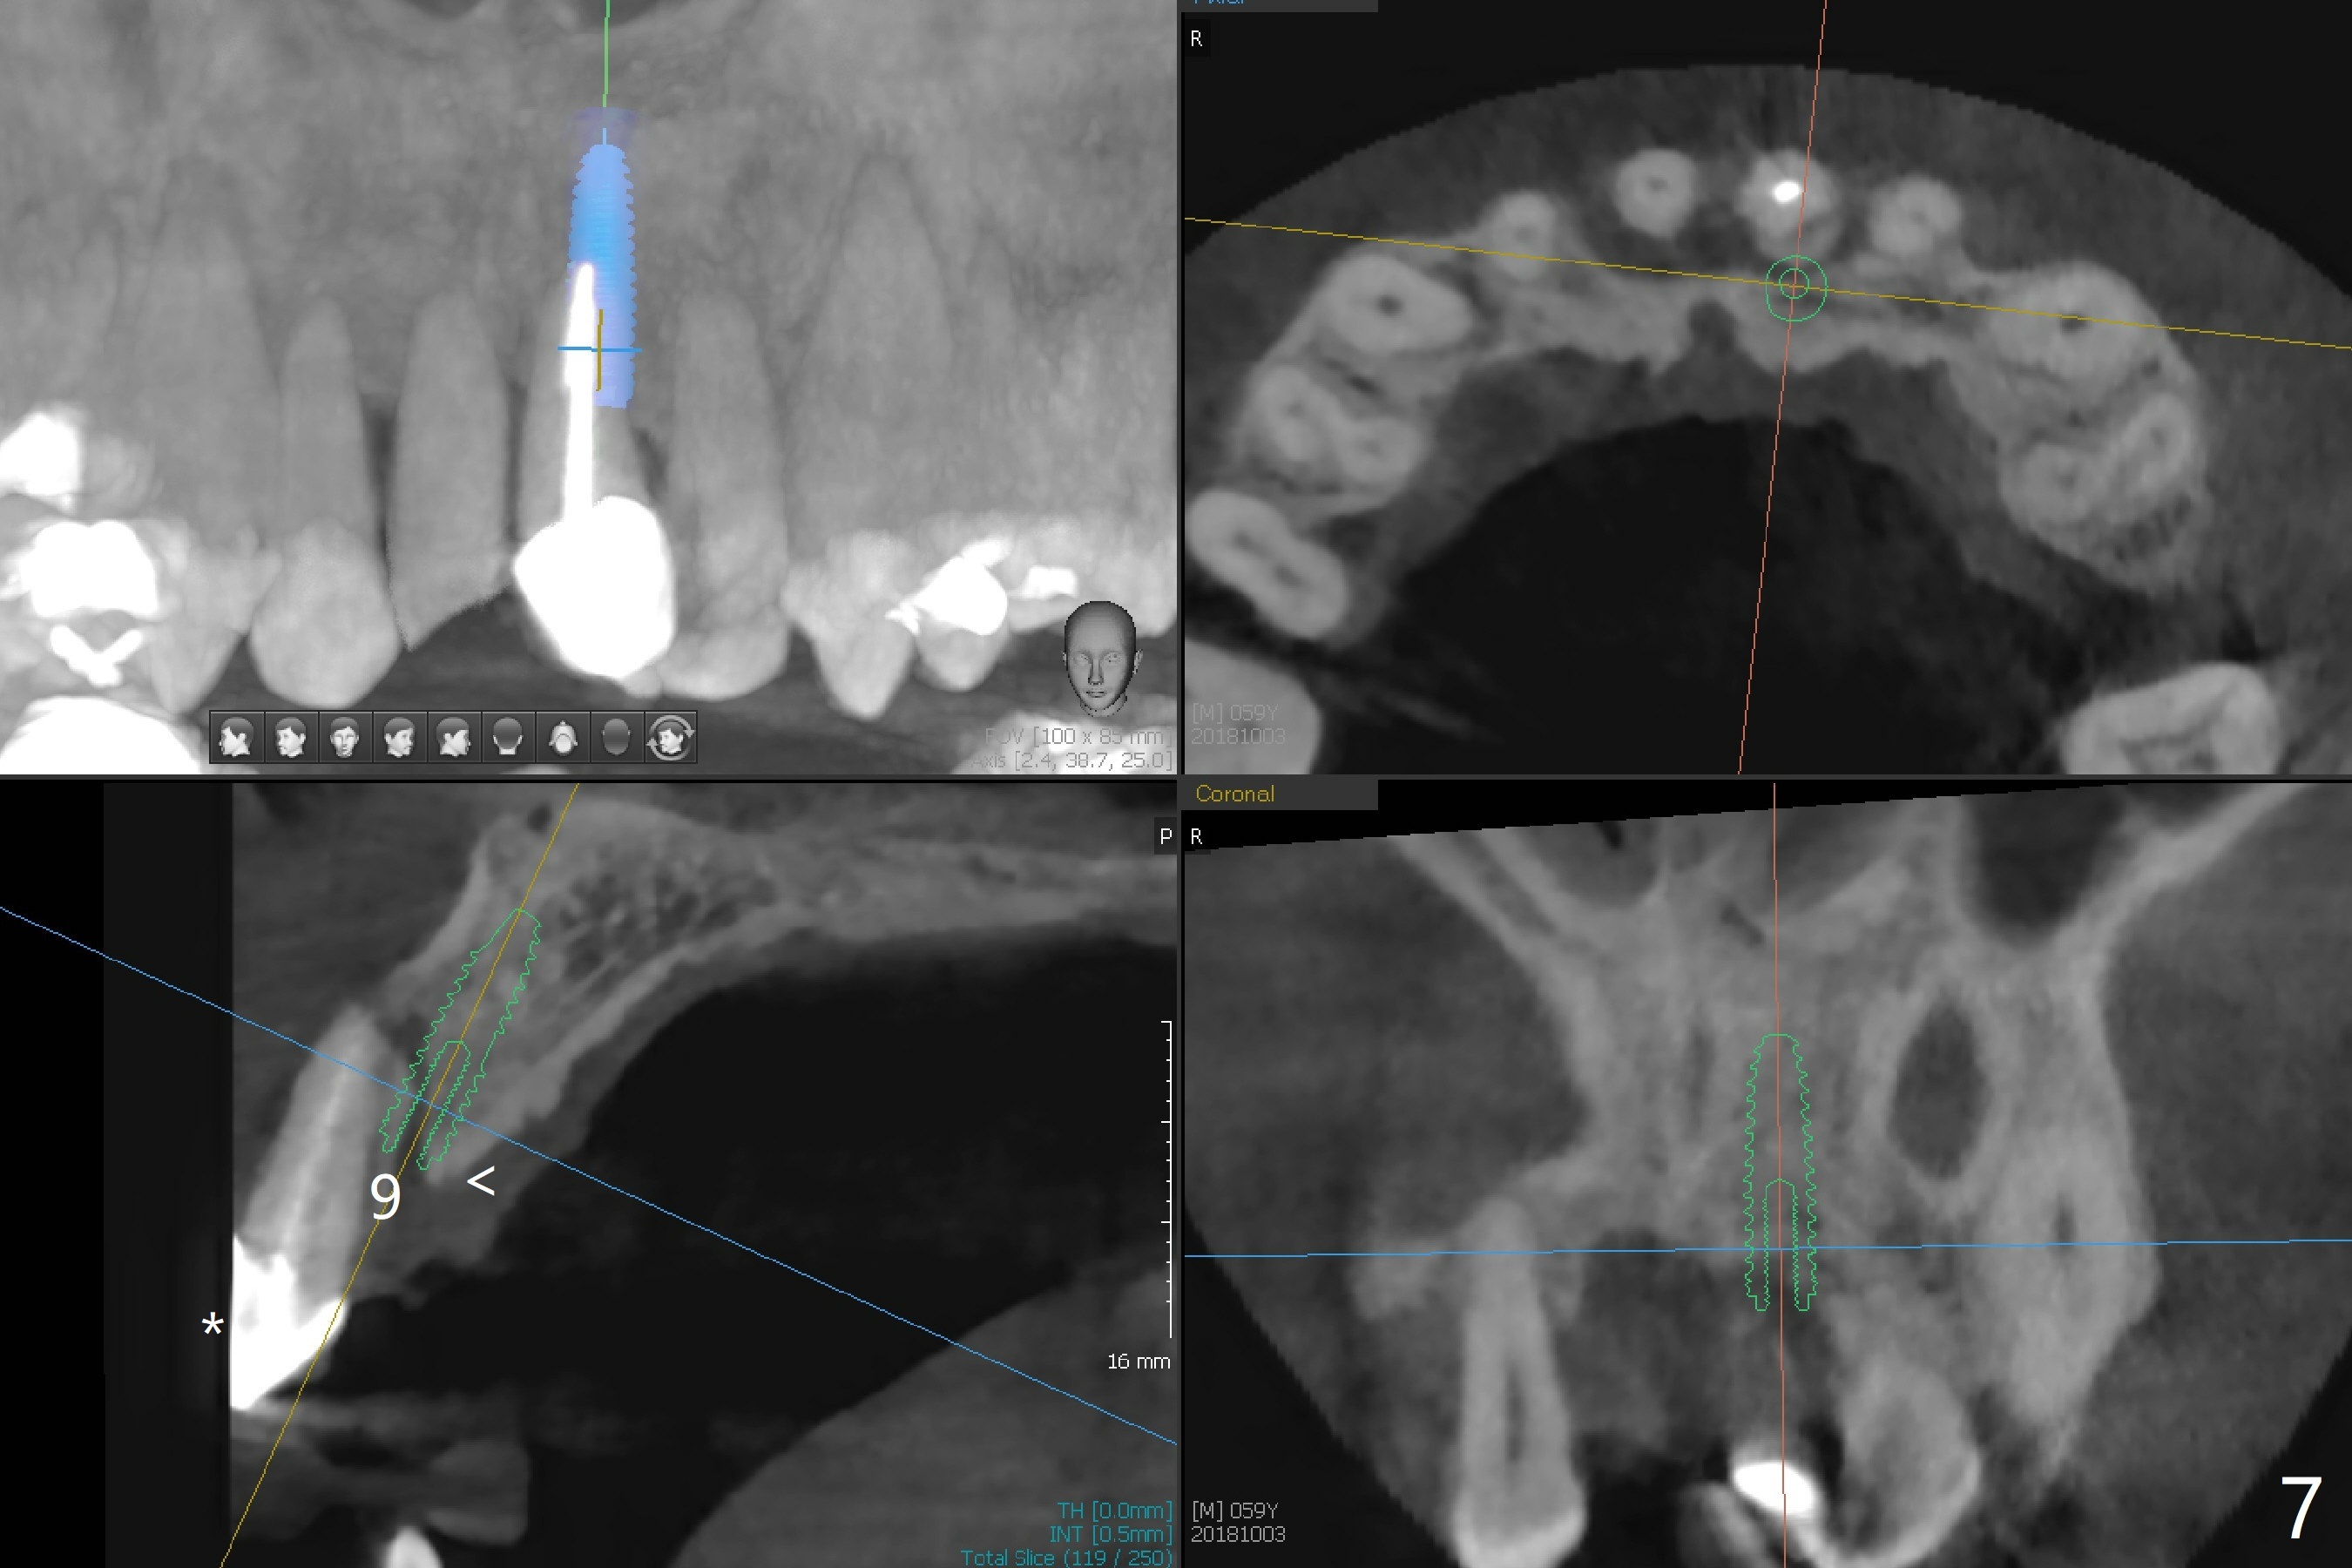

A 59-year-old man requests treatment for buccally displaced upper central incisors (Fig.1,2). It appears that the buccal plate is lost, but the bone height will allow placement of 3.5x13 mm implants with guide (Fig.3). Because of severe infection apical to the tooth #8 (Fig.4,5 *) and truncation of the incisal edges of the upper central incisors during CBCT taking (Fig.6,7 *), guided surgery may not be appropriate. The mesial surfaces of the teeth #7 and 10 and the incisal edges of the lower incisors (*) will be trimmed for immediate provisional. Immediate implants will be placed in the palatal crest of #8 (Fig.6 <) and close to the palatal crest of #9 (Fig.7). Angled abutments are expected (4.5x15 degree, A or B (4 mm cuff). PRF is to be preparedx2 (one for membrane; the other for sticky bone). Take Alginate impression when the patient returns for surgical stent.